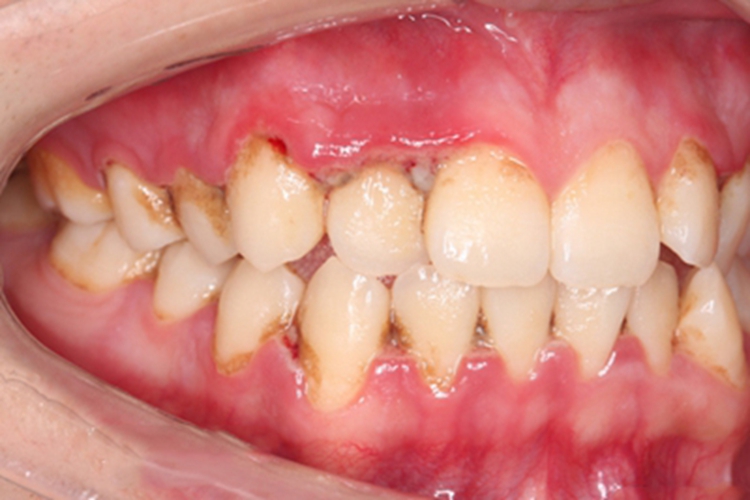

坏死性溃疡性龈口炎可发生于牙龈组织,也就是龈乳头上,局部可见糜烂,边缘不整齐,互相融合形成大片,向周围及深层侵犯,表面可有灰白色假膜,周围牙龈红肿。